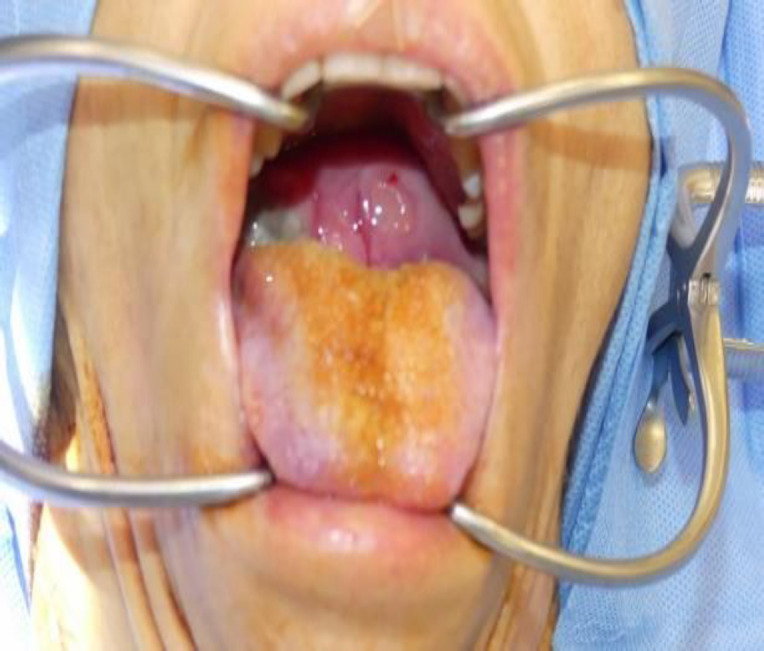

Case report: We described a case of a 39-year-old female presented with a slowly growing mass involving the soft palate. A life-threatening bleeding from PA with hemorrhagic shock occurred and required ligation of the external carotid artery with tracheotomy. A transoral en-bloc excision of the mass (70 x 50 x 40 mm) was performed. Pathological exam demonstrated an atypical PA, with hypercellular fields and myoepithelial and squamous differentiation.